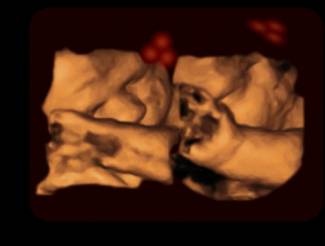

Observación de un feto a través de un ultrasonido 4D. (Foto: Kirsty Dunn & Vincent Reid)

Las películas obtenidas muestran que los bebes se sentían más atraídos por los rostros ‘normales’, que por los invertidos. Con estos resultados, los autores sugieren que los bebes adquieren antes del nacimiento la capacidad para reconocer caras. Además, han comprobado que la luz exterior puede atravesar los tejidos humanos y llegar al útero.